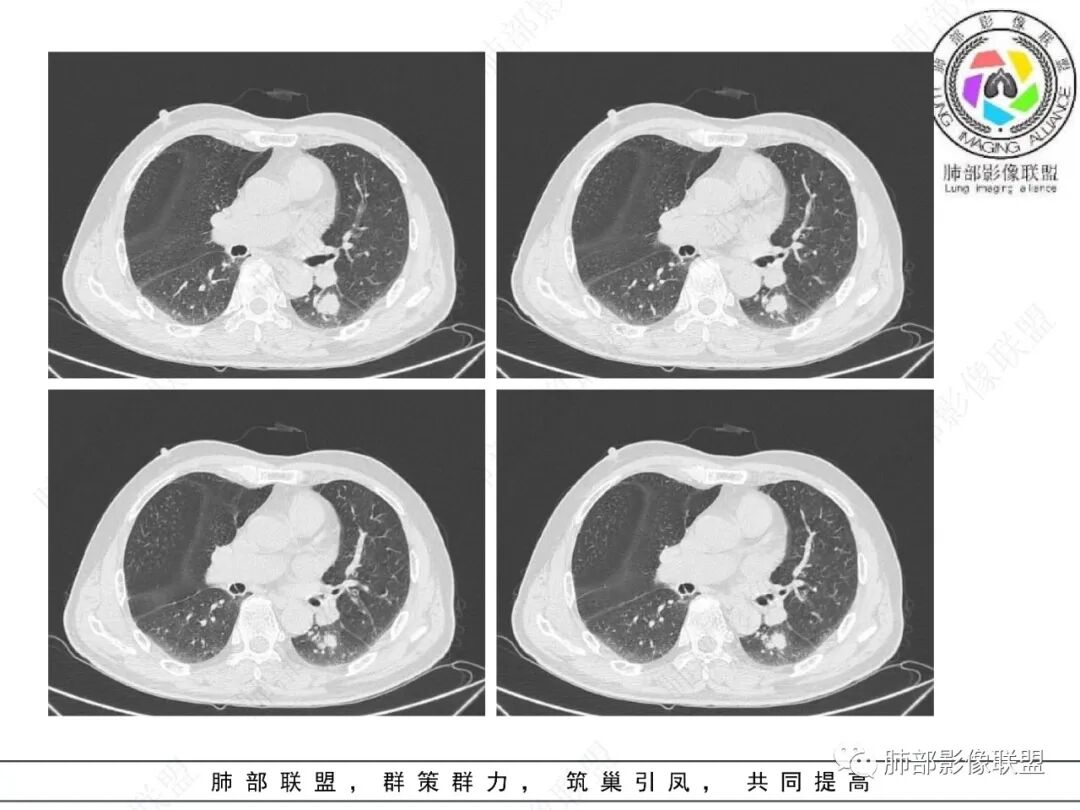

影像学表现:左肺下叶背段近叶间裂旁不规则实性密度结节影,图像未明确显示与支气管关系。边界清,整体膨隆感较明显,边缘显示分叶,偶见段毛刺,叶间胸膜“L”形牵拉凹陷,密度均匀,未见空洞或液化,也未见明显脂肪密度及钙化,轻到中度渐进性强化,未见明确蛇纹状血管应。左肺门可见多发小淋巴结影,纵隔内未见明显肿大淋巴结影。

未见明确卫星灶。